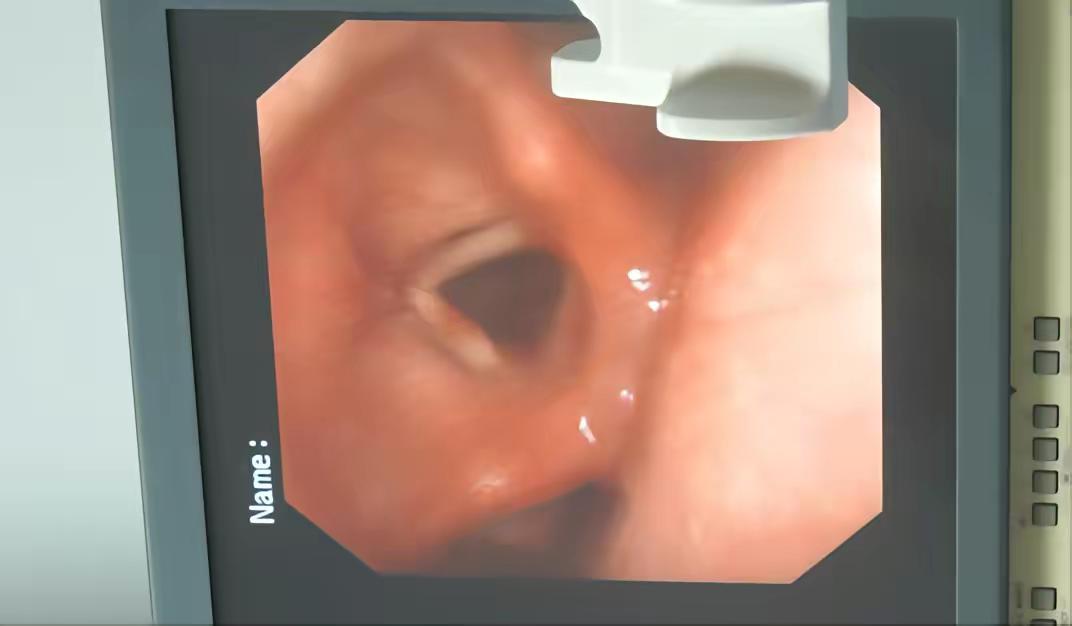

前阵子检测接诊了一个患者,让我心心里忍不住发酸,报告出来的时候,我不知道该怎么给他说。来的是一位66岁的大叔,还有他的妻子一起陪同。他整个人已经苍老得不行,常年处于高强度的劳动,一直都有咳嗽,没有引起重视,也从来没有来医院做过检查,这次是好不容易有了时间,在子女和家人的劝导下来医院检查。我给他做了ct和纤支镜,肺间质纤维化,已经到了中晚期。如果治疗的话,可能面临的医疗费可能对于他们来说是天价,最后人也不一定保得住。可是不治疗的话,在往后的时间里,他也会非常的难受。辛苦一辈子,好不容易熬到了休息的时间,没想到遇到了这个。作为一个医生,即使见惯了生死,可心里这时也忍不住发酸。最后,我没有建议他们彻底治疗,只是开了一些缓解的药,希望最后他能好受一些。这样的悲剧可能每天都在上演,如果能早一些发现,其实完全可以避免。建议看到的朋友,有问题一定要去检查,如果有什么问题或者困难,可以直接联系我,问我。我尽力为大家解答。如果你有报告看不懂,有疑惑也可以发给我帮你看看。医生 医生日常